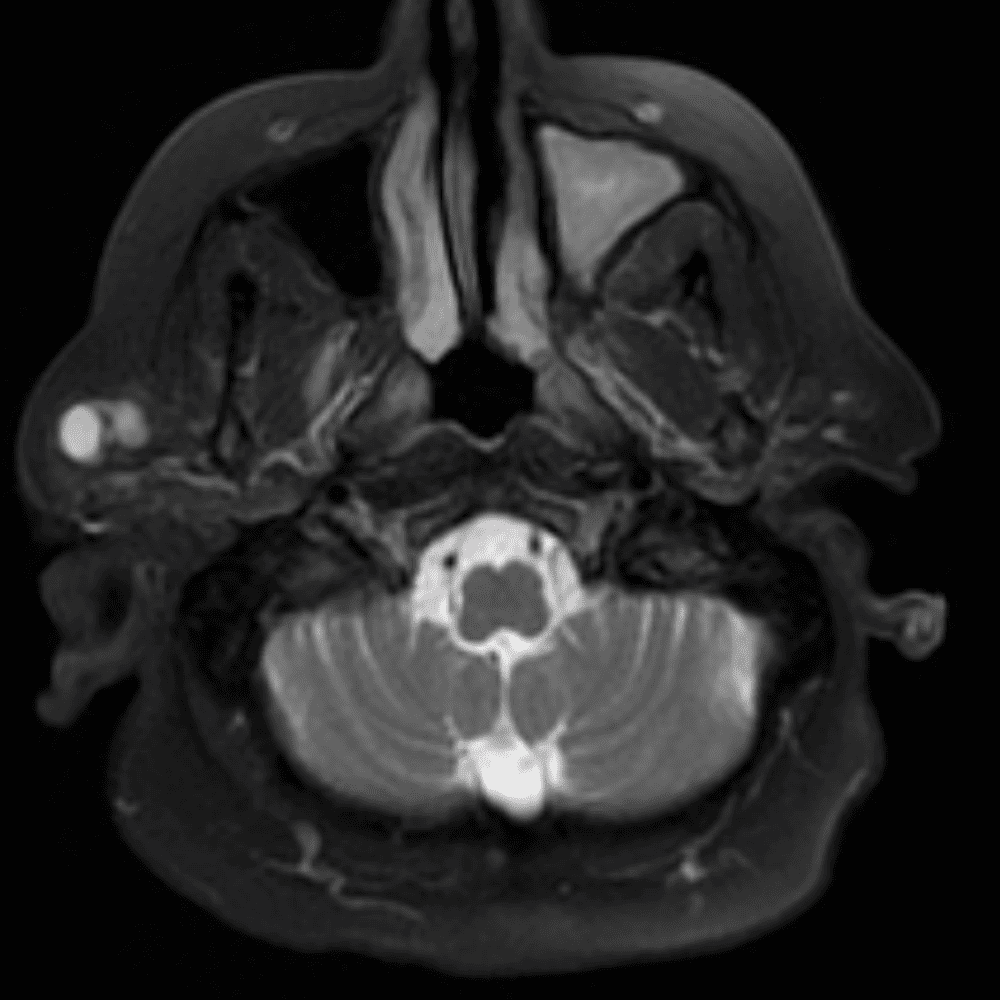

๋‹น์ง ์‹œ ํ”ํžˆ ๋ณผ ์ˆ˜ ์žˆ๋Š” ์‚ฌ๋ก€์˜ ์ „ํ˜•์ ์ธ ์˜ˆ๋ฅผ ํฌํ•จํ•ฉ๋‹ˆ๋‹ค.

39 ์‚ฌ๋ก€

์—ฐ์Šต

๋ฏธ๋ฌ˜ํ•˜๊ฑฐ๋‚˜ ์–ด๋ ค์šด ์‚ฌ๋ก€์™€ ์ผ๋ถ€ ์ •์ƒ ์‚ฌ๋ก€๋ฅผ ํฌํ•จํ•˜์—ฌ ๋‹น์ง์„ ์‹œ๋ฎฌ๋ ˆ์ด์…˜ํ•ฉ๋‹ˆ๋‹ค.

50 ์‚ฌ๋ก€